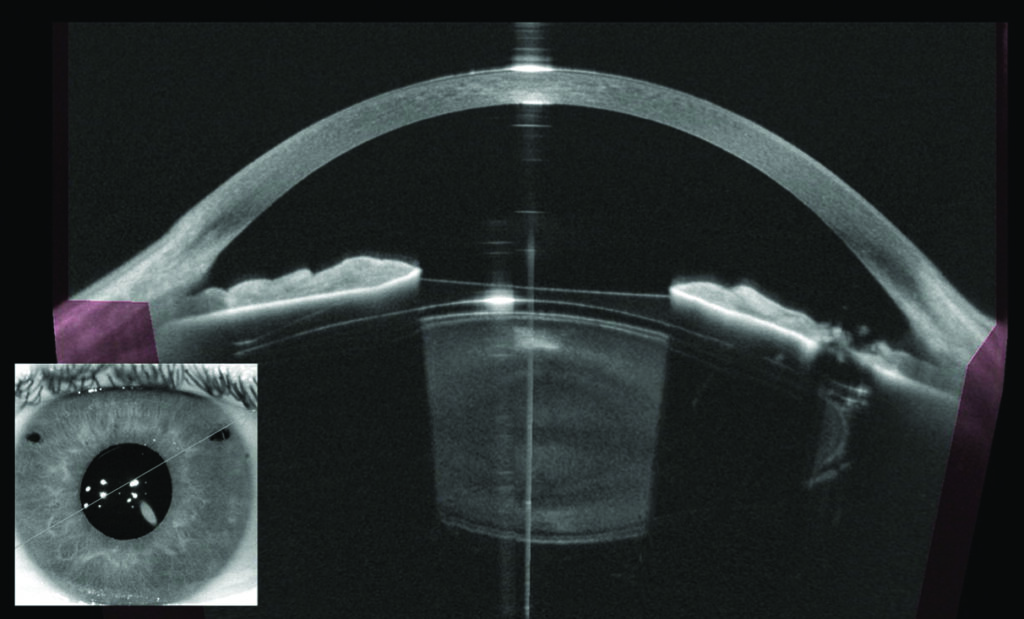

What is an eye scan?

A scan is a visual way of viewing and measuring the inner layers of your eye. The scans can diagnose conditions that are not visible on the surface of the eye and can help to monitor the progression and treatment of the condition.

OCT (optical coherence tomography) scans are the most common types of scans, but you may also have other scans while visiting the eye clinic. All the scans are painless and non-invasive, although we may need to gently lift up your eye lids. The scans only take a couple of minutes.